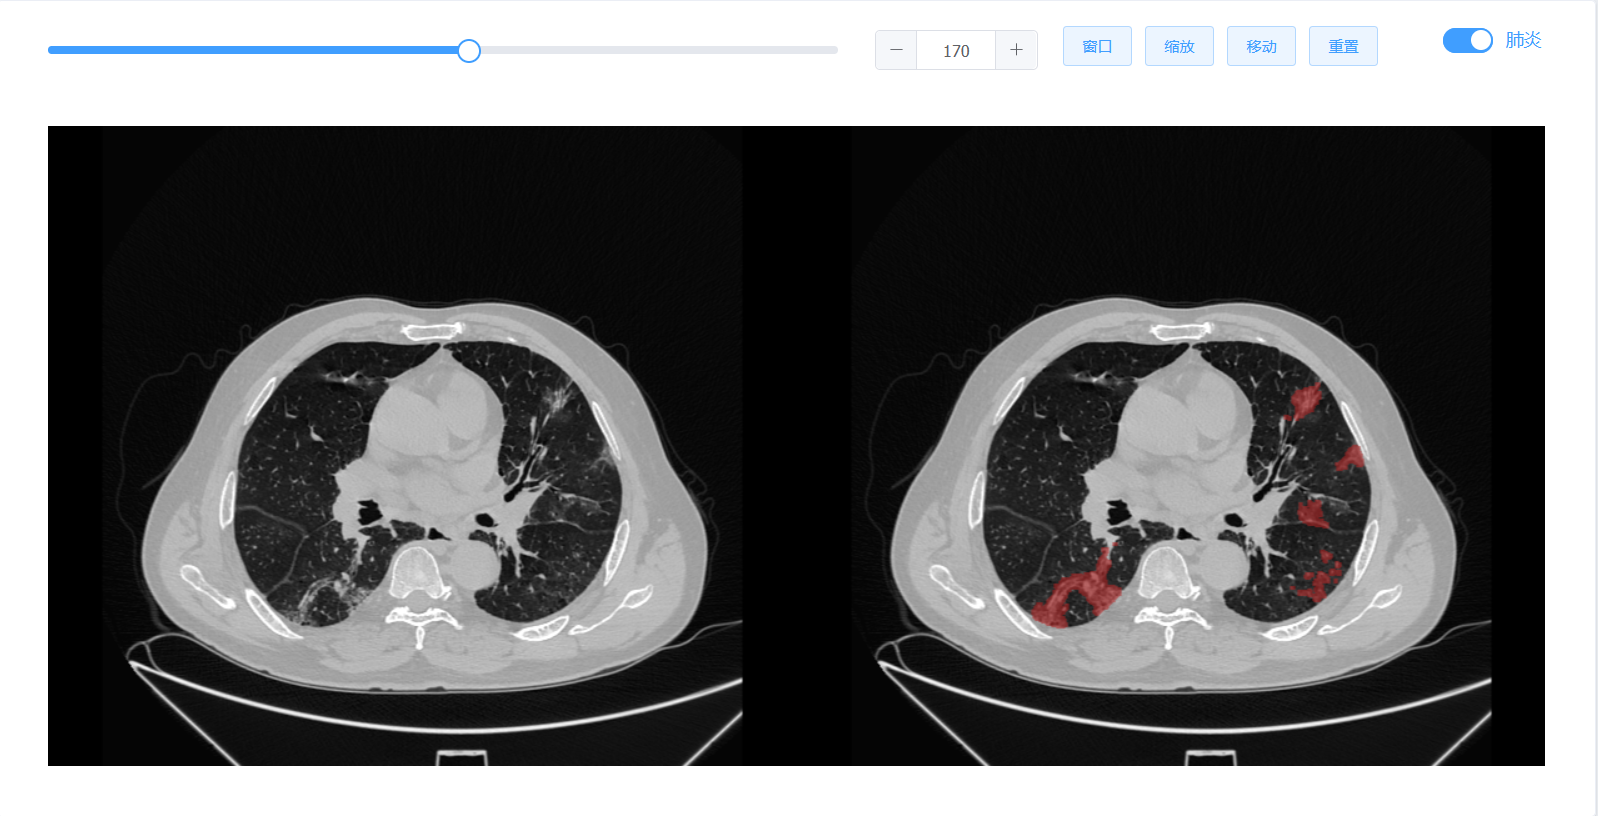

近期,新冠肺炎疫情在国内多地散发,为助力抗击疫情,辅助医生对新冠患者病情有效诊断和治疗,由公司信息与计算机工程公司邱兆文教授团队、哈尔滨工业大学、哈尔滨医科大学附属第一医院、黑龙江拓盟科技有限公司四方合作,成功研发出“新冠肺炎在线建模平台”软件,并已部署到云平台投入应用,可实现2分钟内患者肺部器官和病灶的快速识别,时间效率提升30倍。

该成果研究了高精度快速多期新冠肺炎患者几何模型构建和定量分析算法,研究成果发表在医学影像顶级期刊TMI(IEEE TRANSACTIONS ON MEDICAL IMAGING,IF:10.048)上。目前该系统已经应用在张家界人民医院、哈尔滨医科大学附属第一医院等多家医院。经过科学对比和分析,该系统能够较好实现2分钟内多期新冠肺炎患者肺部器官和病灶的快速识别,并实现三维可视化,时间效率较目前常用影像建模软件提升30倍。极大提升了医生诊断的工作效率,同时能计算出肺炎体积,并进行定量分析,作为诊断的参考依据。该系统还能够支持多期医学影像数据协同管理,多人多机协同操作。